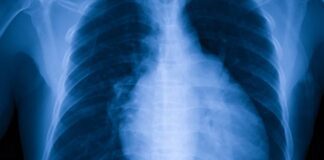

తీవ్రమైన దగ్గు గుండె నిలిచిపోవడానికి సంకేతం కావచ్చు! - Cough May Be an...

దీర్ఘకాలంగా దగ్గు ఇబ్బంది పెడుతోందా.? అయినా దగ్గే కదా, అదే తగ్గిపోతుందిలే అంటూ నిర్లక్షంగా వదిలేసారా.? గృహ చిట్కాలు వాడుతూ వాటి సమస్య తాతాల్కింగా పరిష్కారం అయ్యేలా చేస్తున్నారా.? నిజానికి జలుబుతో పాటు...

కార్డియోమెగలీ అంటే ఏమిటీ? కారకాలు, చికిత్స, ఇంకా - Cardiomegaly (Enlarged Heart): Causes,...

విస్తరించిన గుండె అంటే ఏమిటి? What is an enlarged heart?

కార్డియోమెగలీ అంటే గుండె విస్తరించడం. మరో విధంగా చెప్పాలంటే.. గుండె సాధారణం కంటే పెద్దదిగా ఉందని అర్థం. కండరాలు గట్టిపడేలా పని...